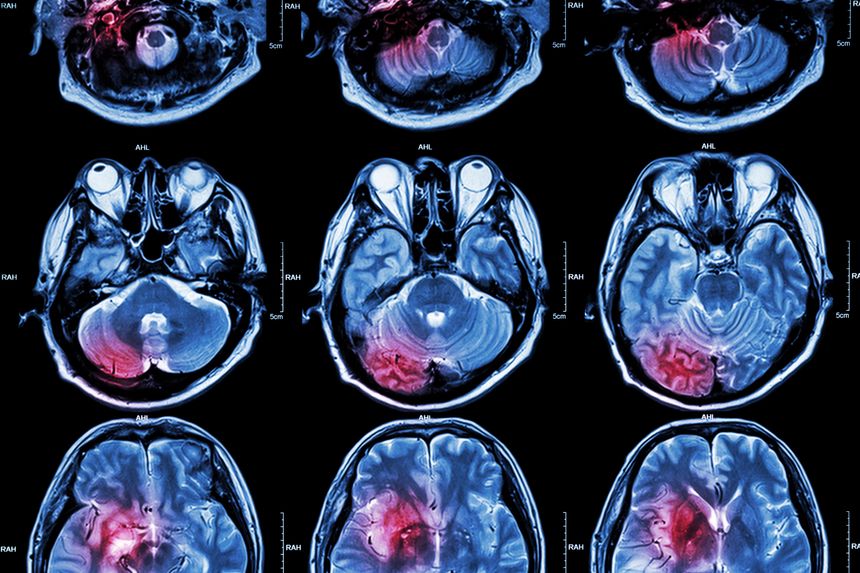

Meningiomas are tumors that develop in the meninges, the protective layers covering the brain and spinal cord. While most are non-cancerous, they can still cause severe health problems, including headaches, seizures, vision changes, and cognitive impairment, especially if they grow large or press on vital brain structures.

If you are experiencing any of these symptoms, it is important to take the next step and speak with a doctor. Your primary care physician can help determine whether imaging, like an MRI or CT scan, is needed to check for brain tumors. If a meningioma is suspected, you may be referred to a neurologist or neurosurgeon for further evaluation and to discuss treatment options, which may include monitoring, surgery, radiation therapy, or other medical interventions.